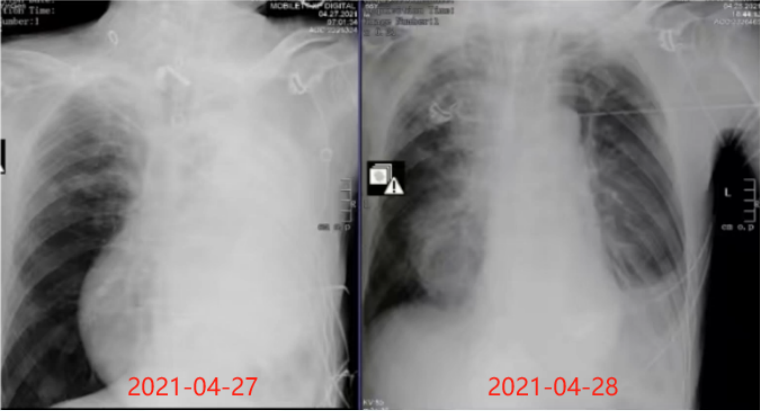

42705:00,患者症状加重,SpO2降至70%血气分析示:pH 7.4PaO2 42 mmHgPaCO2 41 mmHgLac 1.4 mmol/L。当天07:00床旁胸片示:左侧呈“白肺”改变,考虑左肺不张、大量胸腔积液待排(图1)。紧急气管插管接呼吸机支持。插管后完善心脏超声检查:射血分数63%,室间隔基底段增厚,三尖瓣中度反流,轻度肺动脉高压,少量心包积液。

1  患者床旁胸片

4月27日08:00镇静镇痛、肌松、呼吸支持(FiO2 100%,PEEP 12 cmH2O),监护:HR 150次/min,BP 125/80 mmHg[去甲肾上腺素0.8 μg/(kg·min)],SpO2 50%~60%。